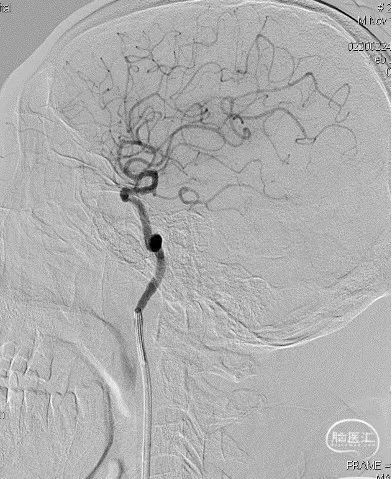

以Transend-14导丝 + Headway21导管到达M1中段,Sofia Plus顺畅到位(M1中段),ADATP技术抽吸取栓,一次成功取通,前向血流TICI 3级,无栓子逃逸及原位狭窄,穿刺至开通时间仅用时9min。

DSA造影见右侧大脑中动脉M1中段以远闭塞,ACA向MCA区域仅少量代偿。Sofia Plus在Headway21导管及Transend导丝引导下,很顺畅通过虹吸段等部位,到达M1中段。

采用ADAPT技术,血流快速复通;最右图为Sofia Plus导管前端及取出血栓。

以Transend导丝 + Headway21导管到达M1中段,Sofia PLUS顺畅到位(M1中段),ADATP技术抽吸取栓,一次成功取通,前向血流恢复至TICI3级,无栓子逃逸及原位狭窄,穿刺至开通时间20min(患者术中间断躁动不配合)。

以Sofia Plus进行抽吸取栓1次(ADAPT技术),实现血流复通(TICI 3级)